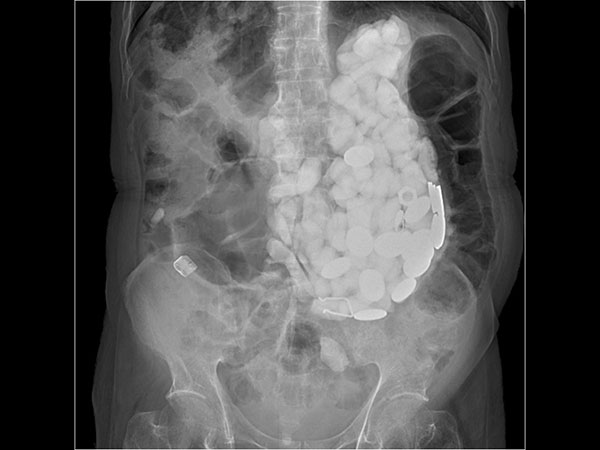

மருத்துவமனையில் மருத்துவர்கள் பரிசோதனை செய்து பார்த்த போது, இவர் மலச்சிக்கலால் பாதிக்கப்பட்டிருந்தது தெரிய வந்தது. அதன்பின் அவருடைய அடி வயிற்றில் தொட்டுப் பார்த்தபோது சிறிய அளவில் ஏதோ கற்கள் போல தென்பட்டிருக்கிறது. அதன்பின் ஸ்கேன் செய்து பார்த்ததில் தான் பேரதிர்ச்சி மருத்துவர்களுக்குக் காத்திருந்தது.

உடனே இதை தாமதித்தால் உயிருக்கே ஆபத்தாகிவிடும் என்று உணர்ந்த மருத்துவர்கள் உடனடியாக அறுவை சிகிச்சை செய்தார்கள். இது மிகவும் சவாலான சிகிச்சையாகவே அவர்களுக்கு இருந்தது. கற்கள் எங்கெல்லாம் சென்று அடைந்திருக்கின்றன என்பதே குழப்பமாக இருந்தது. கேஸ்டிரோதெரபி மூலம் பொருளை வெளியேற்ற முடிவு செய்தனர்.

அறுவை சிகிச்சையின இறுதியில் மருத்துவர்கள் வெளியே எடுத்த பொருள்களைப் பார்த்து அவர்களே அதிர்ச்சியில் உறைந்து போய்விட்டார்கள். ஏனென்றால் கிட்டதட்ட 2 கிலோவுக்கு மேல் கற்களும் காயின் மற்றும் பாட்டில் மூடிகளும் வெளியே எடுக்கப்பட்டிருந்தன.